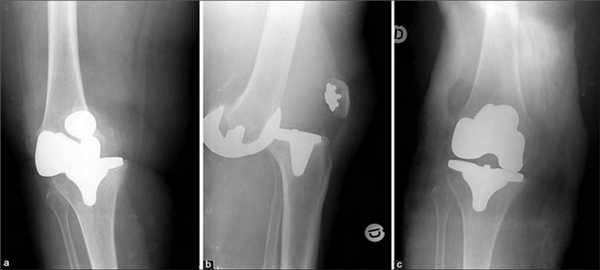

Сложнейшей проблемой ревизионного эндопротезирования коленного сустава является восполнение дефектов бедренной и большеберцовой костей, возникающих в результате остеолиза, при асептическом расшатывании протеза или инфекционном процессе. Дефицит костной массы требует решения вопроса о способе замещения образовавшихся дефектов, восстановления баланса мягких тканей при ревизионной операции и тщательного выбора конструкции эндопротеза.

Используется AORI (Anderson Orthopaedic Research Institute, США) классификация дефектов кости при ревизионном эндопротезировании коленного сустава.

В соответствии с ней выделяют три типа повреждения бедренной или большеберцовой костей:

1 тип - интактная кость

2 тип - повреждённая кость

3 тип - дефицит кости

1 тип - интактная кость (F1 и Т1) - характеризуется относительно нормальной костной структурой и сохранностью губчатой и кортикальной кости метафиза, нормальным уровнем суставной линии. В ходе ревизионной операции при этом типе костных повреждений сохранившаяся губчатая кость может служить опорой как для первичных, так и ревизионных компонентов эндопротеза. Небольшие костные дефекты заполняем цементом или костной алло- и аутокрошкой. Решение о возможности имплантации стандартного эндопротеза или необходимости использования ревизионной модели принимается с учётом состояния коллатеральных связок коленного сустава.

2 тип - повреждённая кость - характеризуется потерей губчатой и кортикальной костной массы без восполнения которой не будет восстановлен требуемый уровень суставной щели. Угловая миграция компонентов эндопротеза обычно приводит к дефекту одного из мыщелков (F2A или Т2А), кость противоположного мыщелка или плато остаётся неизмененной. Симметричная потеря костной массы и вовлечение двух мыщелков или плато обозначаются как F2B и Т2В дефекты. В ходе ревизионной операции для восполнения дефектов бедренной и большеберцовой костей широко применяются ауто- и аллотрансплантаты, модульные блоки или клинья, феморальные и тибиальные метафизарные втулки.

3 тип - дефицит кости (F3 и Т3) - характеризуется выраженной потерей губчатой и кортикальной костной массы, которая приводит к невозможности использования стандартных моделей эндопротезов из-за отсутствия костной опоры. Ревизионная операция при третьем типе повреждения бедренной или большеберцовой костей возможна только при использовании шарнирных имплантатов и восполнении дефектов кости массивными структурными аллотрансплантатами или феморальными и тибиальными метафизарными втулками.